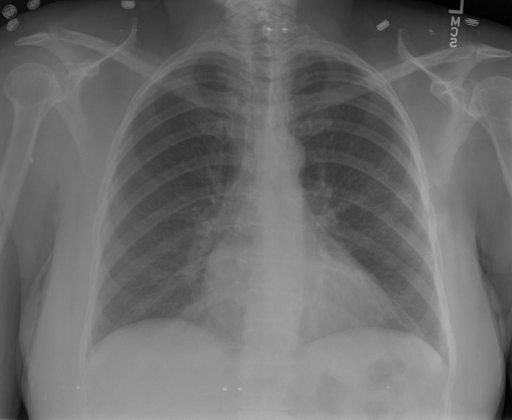

*以下效果来自于**低质量**的数据训练和权重

影像诊断:

|X光影像|诊疗报告(医生)|XrayGLM|

|:-|:-|:-|

||根据X射线图像,心脏大小正常,肺部看起来很清晰。已经排除了肺炎、积液、水肿、气胸、腺病、结节或肿块的存在。该发现表明一切正常。换句话说,总体印象是胸部正常。|X光片显示,心脏大小正常。肺部没有气胸或胸腔积液的证据。骨骼结构看起来没有任何异常。总的来说,X光片表明没有发现急性心肺疾病的迹象。|

||X光图片显示没有扭曲的区域、可疑的骨质不透明度或胸腺积液。心脏大小轻微增大,但非常稳定。此外,没有气胸的证据,肺野也正常。总体来说,X光片显示没有急性心脏异常,但要注意轻微的心脏扩大。|X光片显示,心脏大小正常。肺部和纵隔轮廓清晰,没有气胸或胸腔积液的证据。骨骼结构完整,没有任何急性异常。|

||心影形态在正常范围内。没有急性骨质异常。有可能出现没有明显的吸水或肺实质状况的线索。没有大面积积液或气胸。有可能怀疑其有误吸或肺实质问题。为了确诊和治疗,可能需要进行适当的影像学随访。|心脏大小正常,肺部和纵隔轮廓清晰。没有急性异常或活动受限的证据。没有任何明显的气胸、胸腔积液或肺不张的迹象。此外,也没有发现任何局灶性骨质异常或其他急性疾病。|